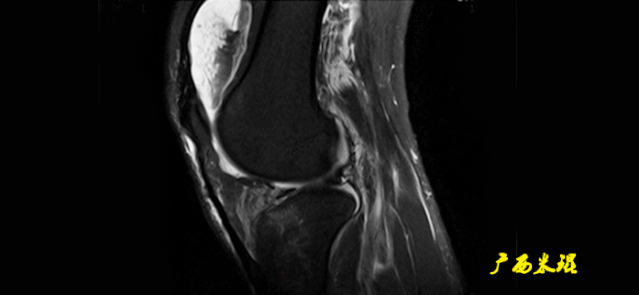

(一)MRI的扫描方向

1.斜矢状面:一般以横断面为定位像,在标准矢状面定位的基础上,将扫描线内旋15°-25°;或以冠状面为定位像,平行于韧带长轴进行扫描。

2.斜冠状面:一般以矢状面为定位像,沿韧带长轴进行扫描。

3.轴状面:扫描层面平行于膝关节间隙。

(四)ACL最好的观察层面

-

最好的观察层面是斜矢状面。

必须结合横断面和冠状面。

(五)ACL角度

矢状面ACL与髁间窝的顶部形成一个13°的夹角。